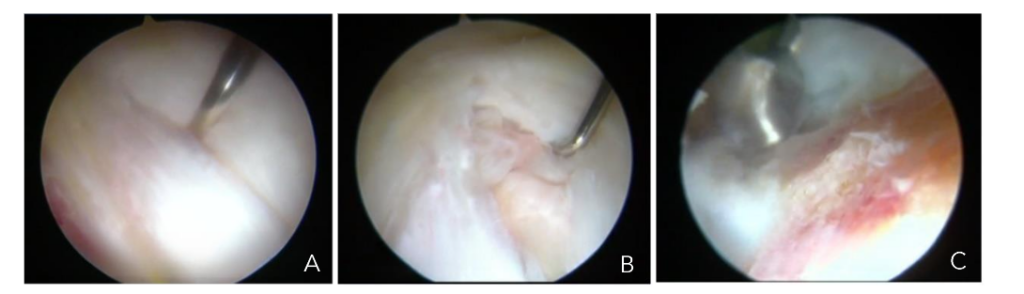

Complete rupture of the gluteus medius tendon presents a significant challenge for surgeons, as the tendon has been displaced from its anatomical position in the greater trochanter, which is typically sclerotic and is associated with a tendon of poor quality. Poor outcomes have been reported with conventional open surgical treatments in such cases. Consequently, we have developed an endoscopic surgical technique, as described for partial tendon lesions, with the notable distinction that in these cases it is crucial to examine the continuity of the tendon with the bone tissue and assess its adherence or detachment. If the tendon is detached, it must be incised longitudinally to identify the sclerotic zone of the bone at the greater trochanter, which is then removed, typically with a 5.5 mm burr drill, to create a bleeding bed where the tendon can heal. The tendon is subsequently fixed with one or two 5.5 mm titanium anchors loaded with double sutures to close the incision and secure the tendon to the bleeding bed of the greater trochanter Figure 9a-c and 10a-d.

Figures 9a-c. Endoscopic view of a longitudinal incision of the gluteus medius tendon (A), exposure of sclerotic bone beneath the tendon (B), bone bed preparation under tendon (C).